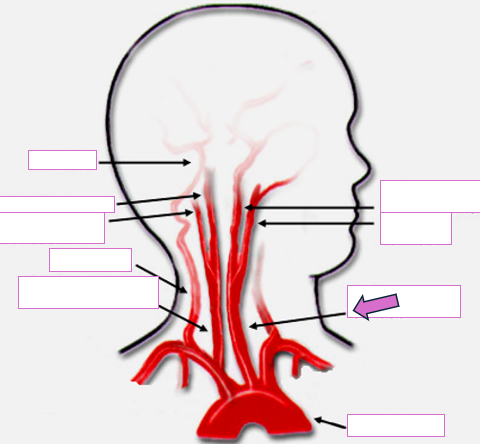

Based on the indicated area, identify this vessel

Brachiocephalic/innominate artery

Right subclavian artery

Right vertebral artery

Right carotid artery

Left carotid artery

Left vertebral artery

Left subclavian artery

Aortic arch